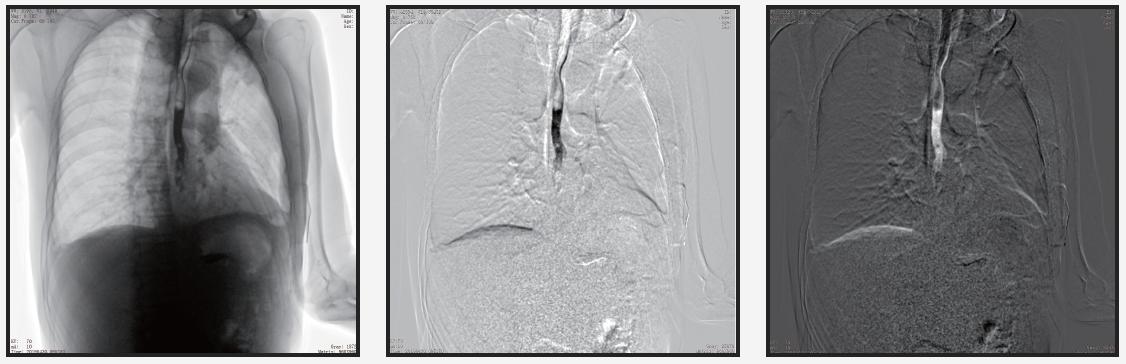

自主研發(fā)的組織均衡技術(shù)

人體圖像通過組織均衡后,圖像細(xì)節(jié)更突出,肺紋理末端細(xì)小血管及骨骼的紋理、肌肉層次等均可清晰顯示。